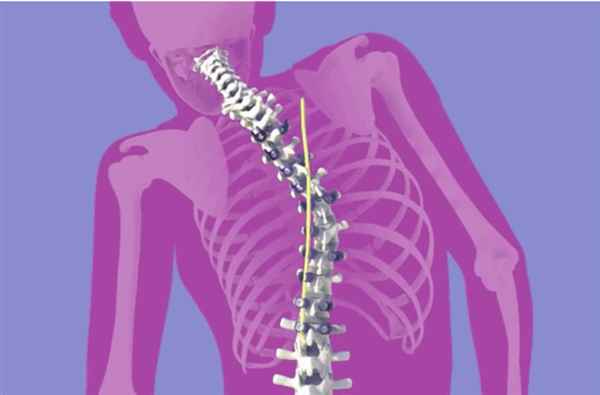

Клинический пример: больная Н., 1999 г.р., прооперированная по поводу сколиотической болезни (рис.1-4):

Рис.4. Передняя и боковая спондилограмма после операции